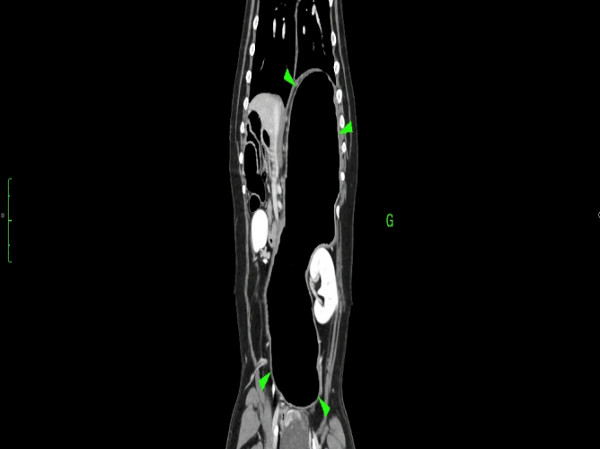

Trois cas résultent de l'extension d'une otite. Ces patients étaient présentés pour ataxie et l'un d'entre eux présentait également des crises convulsives partielles. Dans les trois cas, un examen scanner a mis en évidence une otite moyenne associée à une lésion intracrânienne extra-axiale adjacente, évoquant un empyème méningé. Dans le premier cas, un traitement antibiotique probabiliste permet la résolution des signes cliniques. Dans le deuxième cas, des prélèvements par vidéo-otoscopie permet d'identifier la présence de Staphylococcus felis. Un traitement antibiotique ciblé entraîne la résolution des signes cliniques. Dans le troisième cas, l'examen vidéo-otoscopique permet l'identification de Pseudomonas spp. Malgré une antibiothérapie adaptée, l'état clinique du patient se détériore. Un nouvel examen scanner montre une aggravation de l'empyème méningé. Une craniotomie est réalisée et permet le débridement de l'empyème. Cette intervention, associée à une corticothérapie et la poursuite de l'antibiothérapie, permettent la résolution des signes cliniques.

Nous présentons également un cas d'extension d'une rhino-sinusite infectieuse chez un chat présentant une ataxie. Un scanner montre des lésions naso-sinusales agressives avec lyse de la paroi sinusale frontale et empyème méningé adjacent. Une trépanation du sinus frontal permet de réaliser des prélèvements pour analyses bactériologiques et mycologiques. Un traitement antibiotique ciblé permet une bonne évolution clinique.

Le dernier cas de notre étude est un chat présenté pour ataxie et dont le scanner montre une fracture ponctiforme de l'os pariétal gauche du crâne avec abcès intracrânien et sous-cutané, probablement secondaires à un traumatisme. Un traitement médical est mis en place. Après une amélioration transitoire de son état général, le patient décède trois jours plus tard.

De ce fait, les examens d'imagerie en coupes sont essentiels pour diagnostiquer les abcès intracrâniens. Nous rapportons leur aspect au scanner mais détaillons également leurs caractéristiques à l'examen d'IRM.